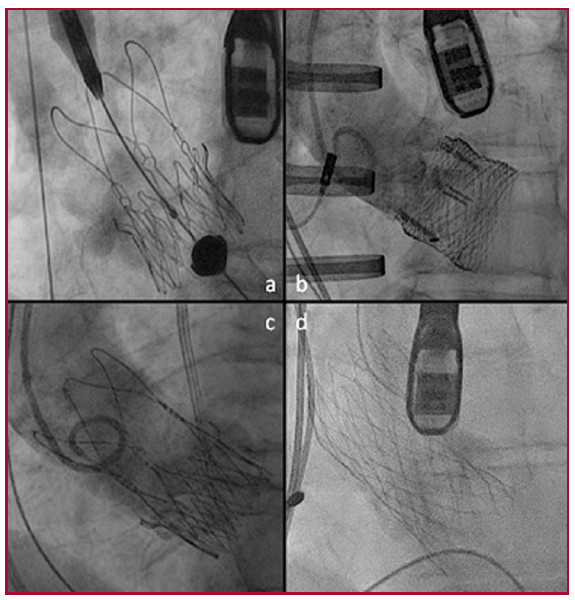

Revisamos retrospectivamente los registros de 89 pacientes con estenosis aórtica grave sintomática tratados con TAVI en el Hospital Italiano de Buenos Aires, Argentina, entre marzo del 2009 y abril del 2016 inclusive. Se seleccionaron aquellos pacientes sometidos a TAVI-TA (n = 24) y TAVI-TF (n = 56) y se excluyeron pacientes con otros abordajes, como transaórtico, transilíaco o transubclavio (n = 9). Las bioprótesis valvulares utilizadas para el abordaje TA fueron Acurate TA® (Symetis), mientras que las utilizadas para el abordaje TF fueron CoreValve® (Medtronic), Accurate Neo® (Symetis) y Lotus® (Boston Scientific) según criterio del grupo tratante (Figura 1).